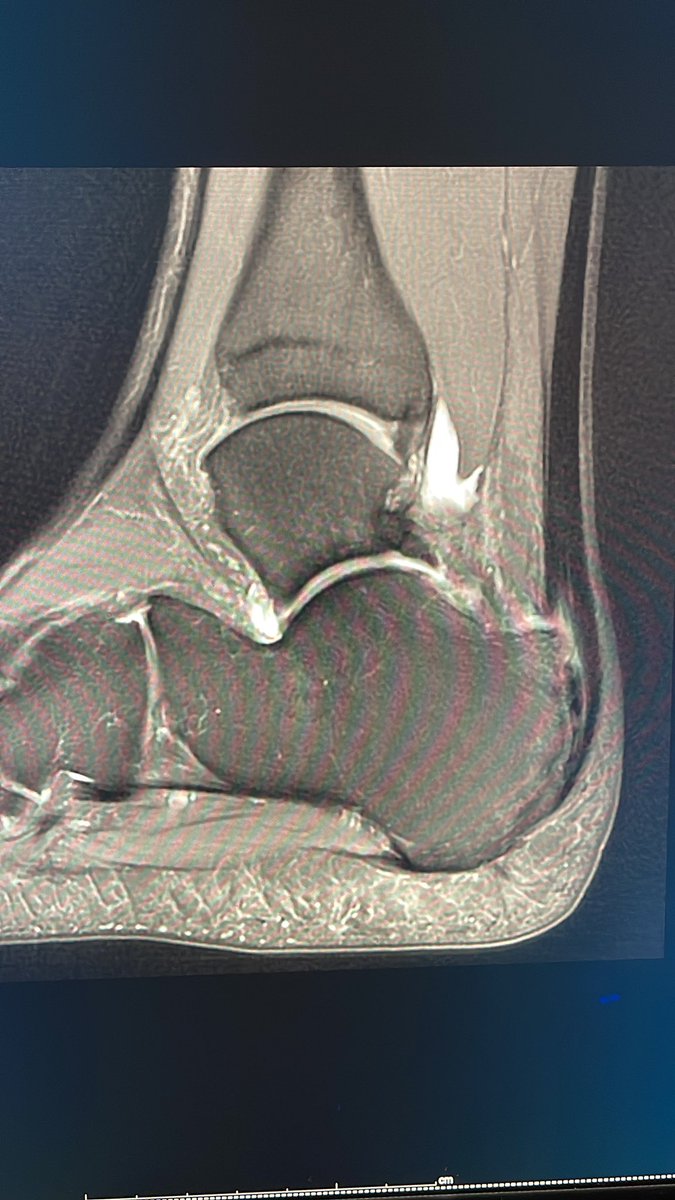

Achilles’ tendon rupture in soccer player. MR in 2020 versus 2022 shows progression to full thickness tear of distal Achilles’ tendon. The distal 2.5 inches is most prone to rupture especially in the setting of chronic trauma due to less blood flow which may also impair healing.